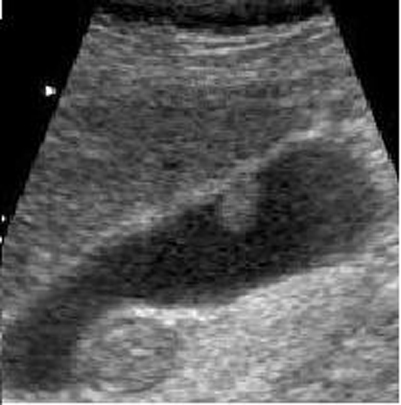

Adenome pedicule

de forme tubulaire . Aspect de adenomeme est

isoechogenique colletant au paroi par une pedicule .

Image echographique en coupe longitudinale de la

vesicule biliaire |